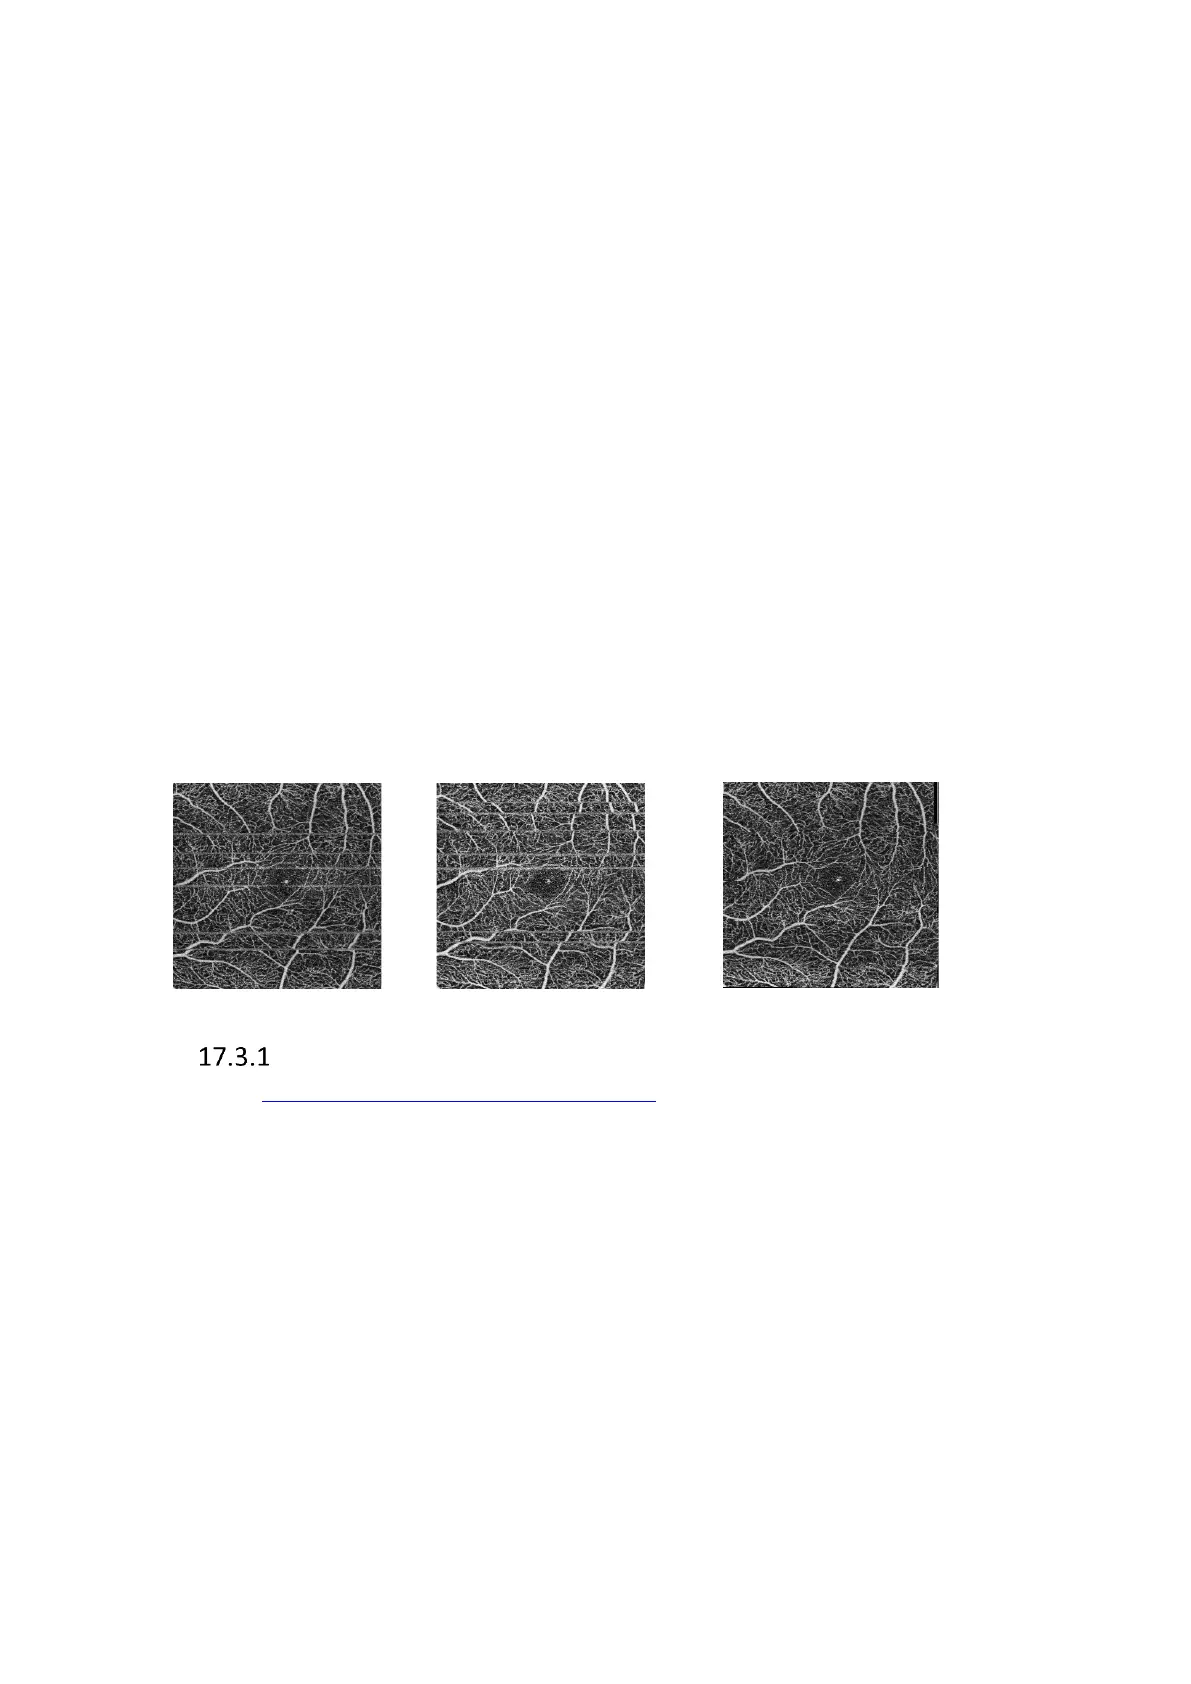

Figure 250. Example of Motion Corrected examination

Exam 1

Exam 2

MC Result